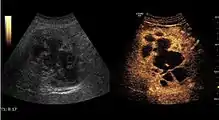

Benign focal nodular hyperplasia (CEUS). Gray scale examination (left) detects the lesion. CEUS examination (right) allows characterization of tumor nature based on central contrast enhancement and centrifugal dispersion.

It is a tumor developed secondary to a circulatory abnormality with abundant arterial vessels having a characteristic location in the center of the tumor, within a fibrotic scar. A radial vessels network develops from this level with peripheral orientation. The tumor's circulatory bed is rich in microcirculatory and portal venous elements. The incidence is higher in younger women and tumor development is accelerated by oral contraceptives intake. 2D ultrasound appearance is a fairly well-defined mass, with variable sizes, usually single, solid consistency with inhomogeneous structure. Rarely the central scar can be distinguished. Spectral Doppler examination detects central arterial vessels and CFM exploration reveals their radial position. CEUS examination shows central tumor filling of the circulatory bed during arterial phase and completely enhancement during portal venous phase. During this phase the center of the lesion becomes hypoechoic, enhancing the tumor scar. During the late phase the tumor remains isoechoic to the liver, which strengthens the diagnosis of benign lesion.